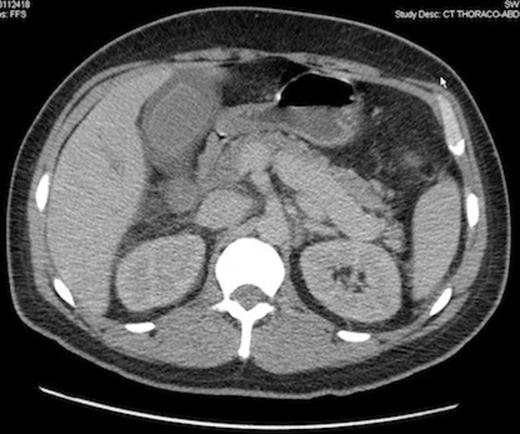

Computed tomography scan demonstrating gallbladder wall thickening and pericholecystic liquid, without gallbladder lithiasis, confirmed by ultrasonography.

One month later the first consolidation chemotherapy (cytarabine + amsacrine) was done and 6 days afterwards the patient presented diarrhoea without abdominal pain or fever. The laboratory investigations revealed a total leukocyte count of 500/mm3, a haemoglobin level of 68 g/L and a platelet count of 11 000/mm3. Despite supportive treatment and antibiotics for a supposed improving colitis, the patient complained of right upper quadrant abdominal pain, high fever (40°C) and hypotension needing ICU admission with the diagnose of abdominal sepsis. A positive Murphy’s sign was observed at physical abdominal examination. The radiological imaging was suggestive for an alithiasic cholecystitis, even though a transverse colon wall thickening was also seen in computed tomography.